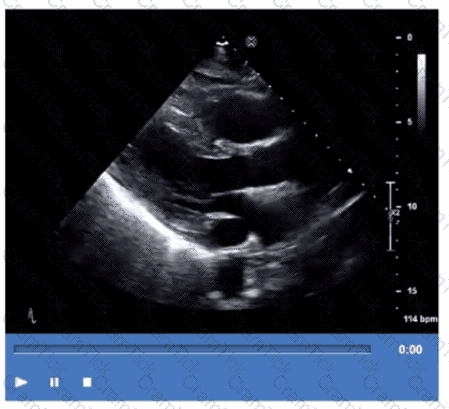

Which step is next in further evaluation of the abnormality shown in this video?

Which is the most likely abnormality represented in these images from a 48-year-old man with shortness of breath?